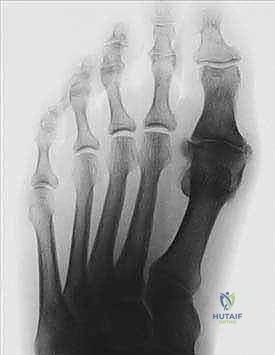

- التصوير بالأشعة السينية (X-rays): تُعد الأشعة السينية أثناء الوقوف (Weight-bearing X-rays) الأداة الذهبية لتشخيص إبهام القدم المتيبس. فهي تظهر بوضوح مدى تضيق المسافة المفصلية، حجم وموقع النتوءات العظمية، ودرجة تآكل الغضروف.

| المرحلة 1 | ألم متقطع، تيبس خفيف، ألم عند أقصى ثني للإصبع. | بداية ظهور نتوءات عظمية صغيرة (Osteophytes)، تضيق طفيف في المسافة المفصلية. |

| المرحلة 2 | ألم مستمر يزداد مع الحركة، صعوبة في ارتداء بعض الأحذية، محدودية واضحة في الحركة. | تضيق واضح في المسافة المفصلية، نتوءات عظمية متوسطة على ظهر المفصل. |

| المرحلة 3 | ألم شديد ومستمر، تيبس شبه كامل، ألم حتى عند الراحة، بروز عظمي كبير. | تآكل شديد أو اختفاء للمسافة المفصلية، نتوءات عظمية كبيرة محيطة بالمفصل، تكيسات عظمية. |

| المرحلة 4 | نفس أعراض المرحلة 3، ولكن مع ألم شديد طوال نطاق الحركة (حتى الحركات البسيطة جداً). | دمار كامل للمفصل، احتكاك عظم بعظم (Bone-on-Bone)، نتوءات ضخمة. |